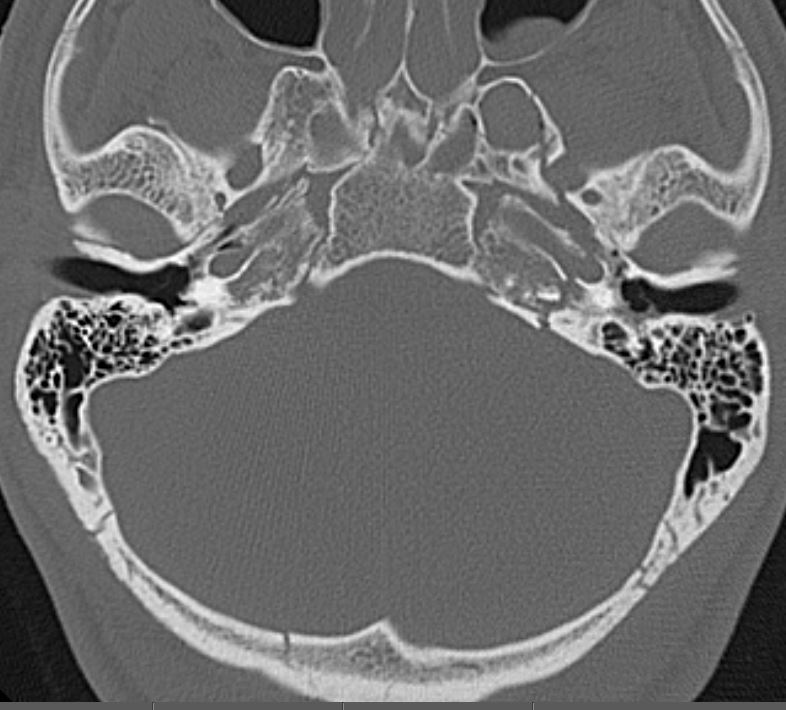

Central Skull Base and Calvarium

Mandible and Temporomandibular Joints